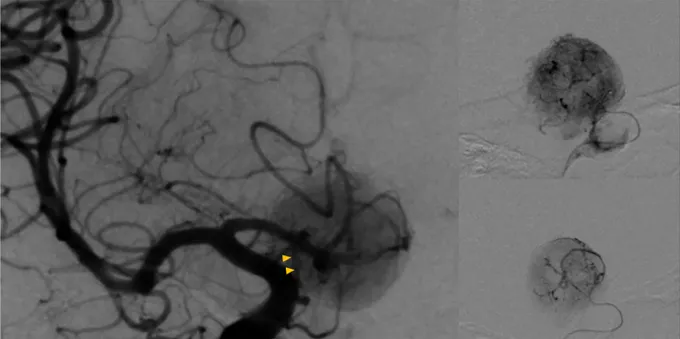

具体分析:由于已知该肿瘤的血供丰富,福教授在手术前进行了DSA检查,显示其供血动脉主要为左侧垂体上的动脉(黄色箭头)。

要求:切断肿瘤的血供,避免术中出血。

福教授策略:进行术前栓塞确定供血动脉,且对颅底硬脑膜分支血管的近端闭塞对神经缺血的风险较小。栓塞后的血管造影显示肿瘤的供血动脉重建达到90%,线圈在垂体上动脉内可见(黄色箭头)。